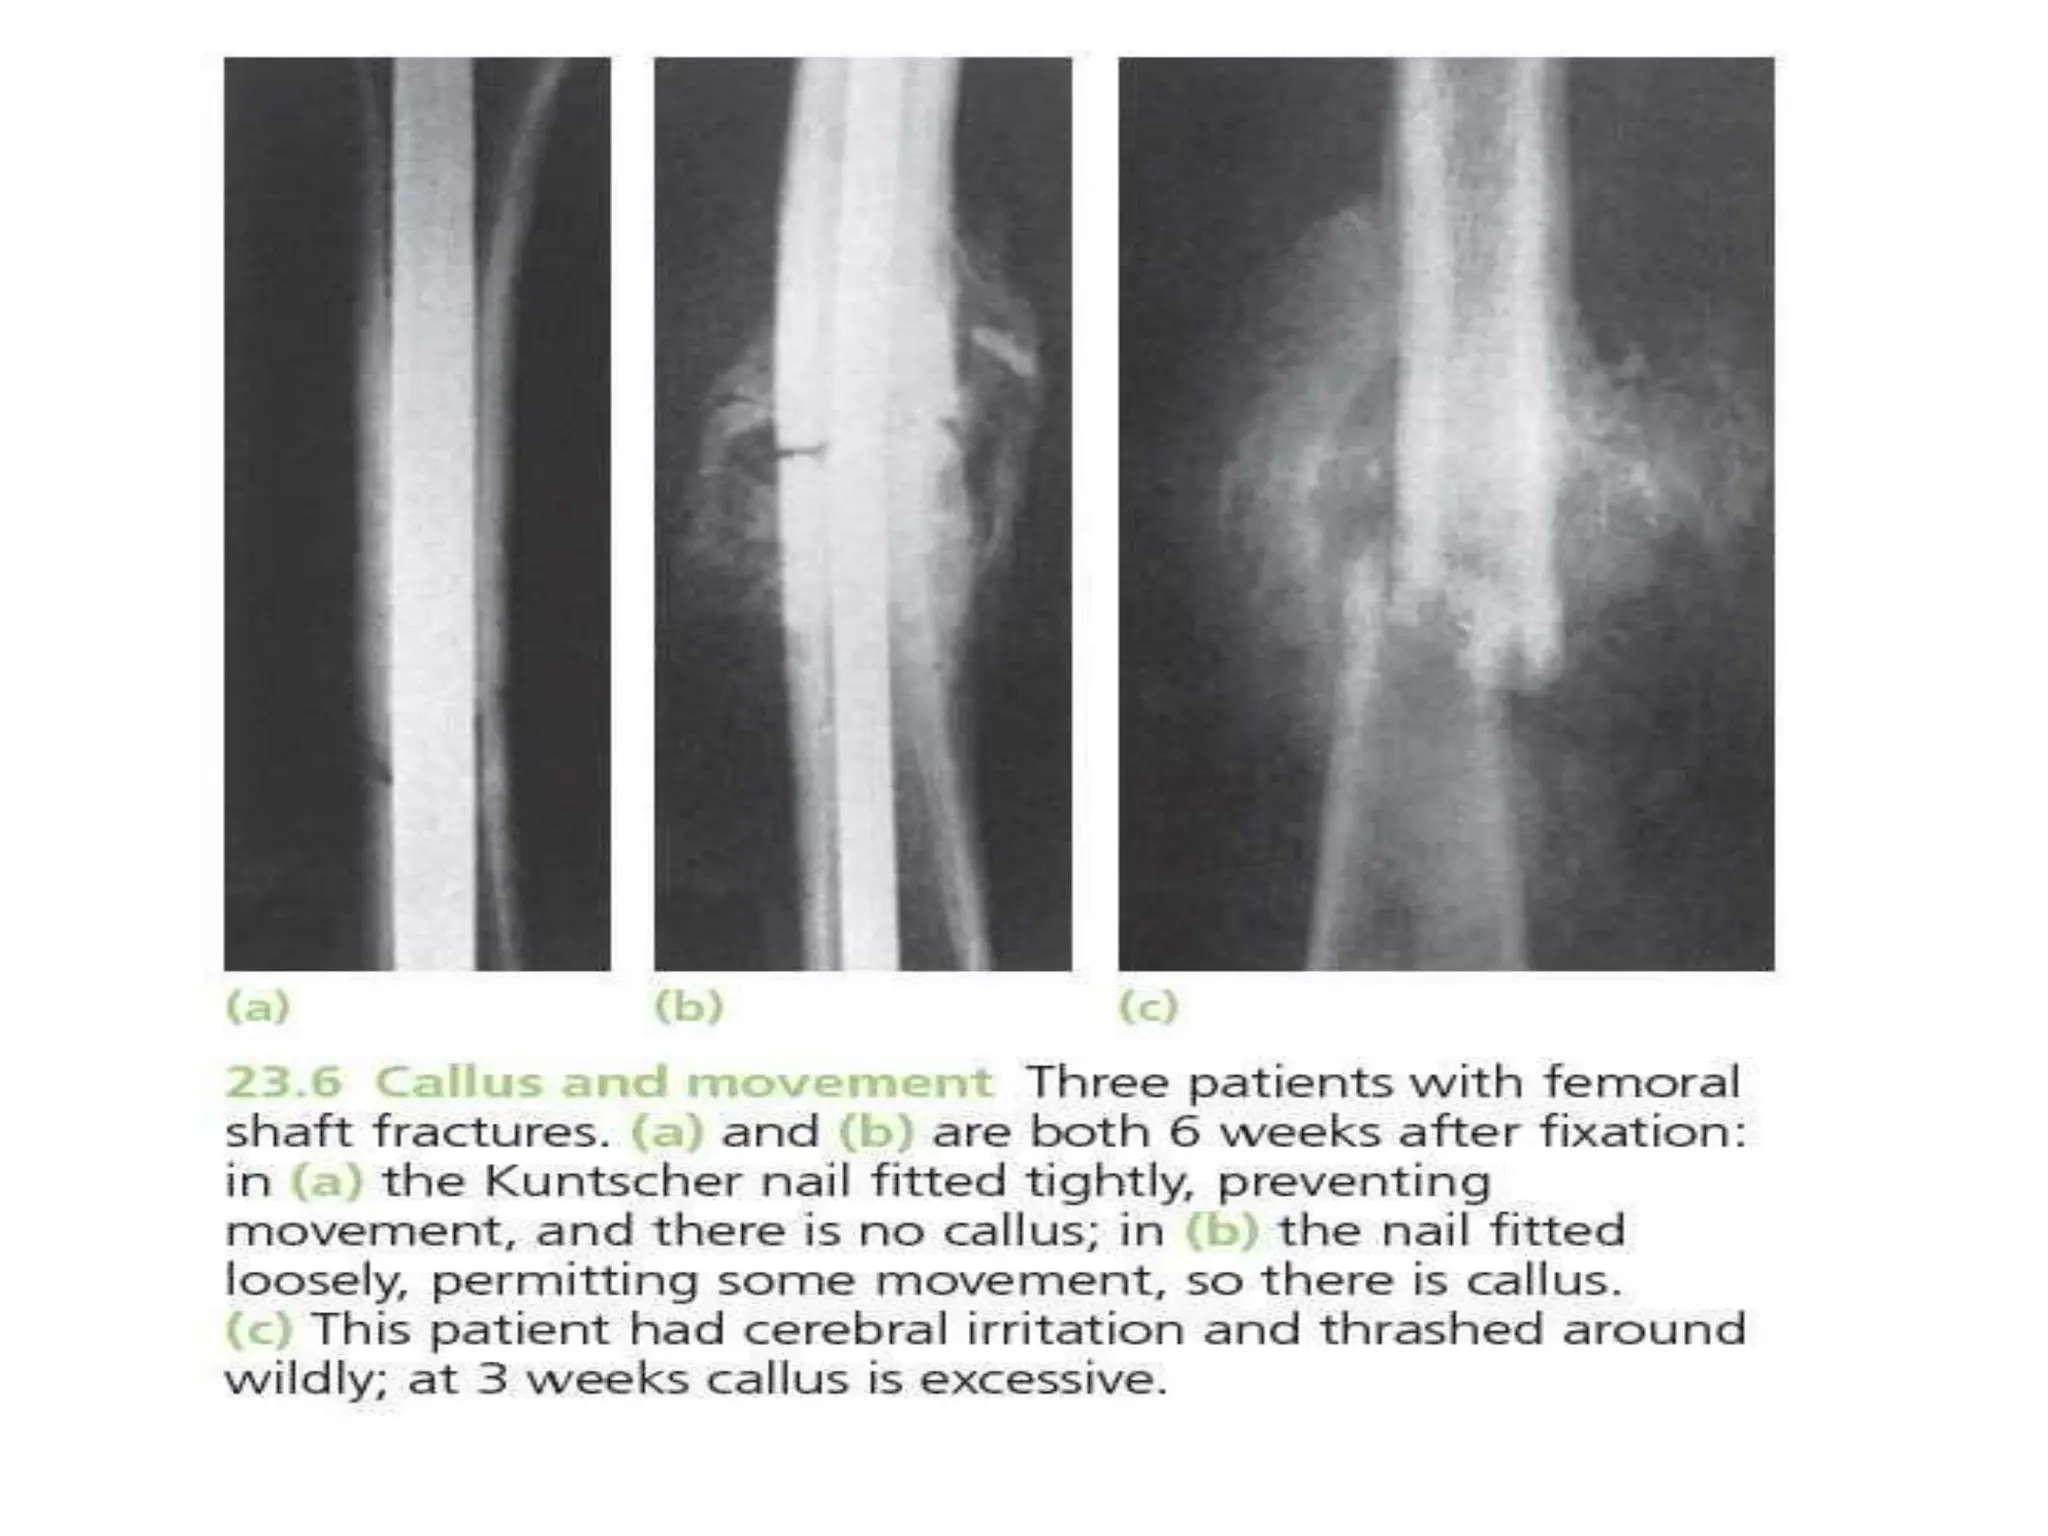

HEALING BY DIRECT UNION

• Formation of callus requires stimulus from

movement

• In cases of impacted fracture in cancellous

bone or a fracture immobilised by the use of

metal plate, callus will not be formed and

hence the fracture will heal by direct union